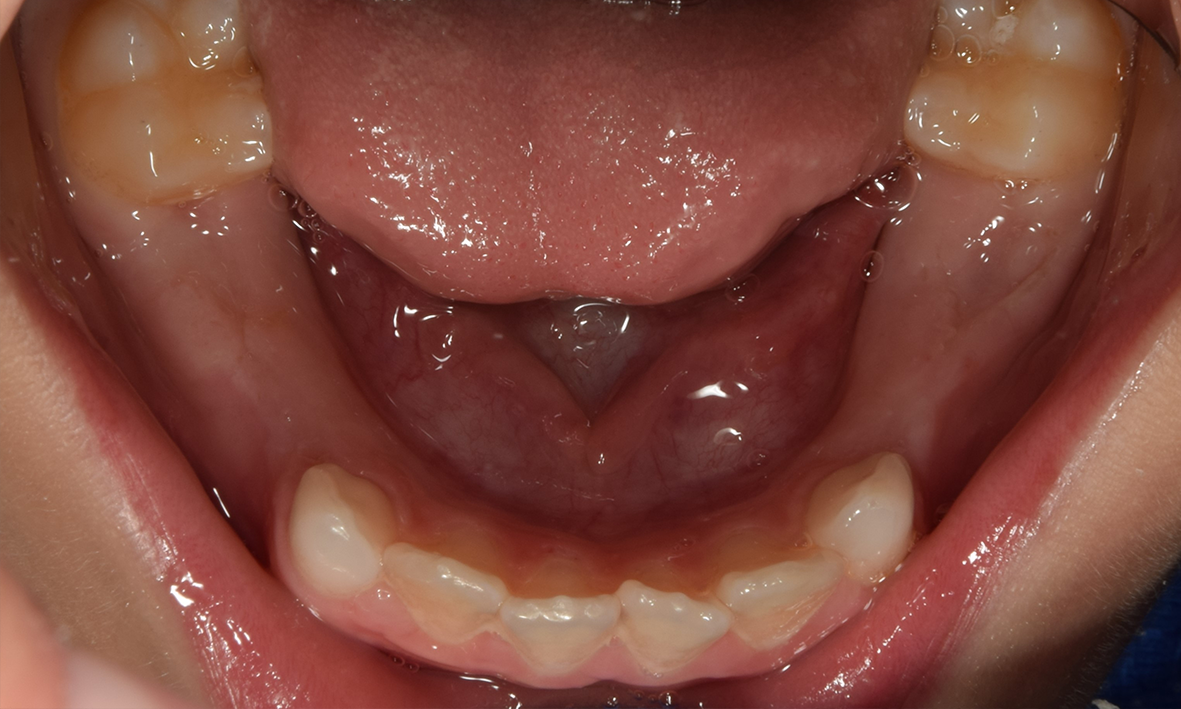

• A helyhiány miatt a maradófog vagy az állcsontban ragad (felső szemfogaknál nagyon gyakori), vagy rendellenes pozícióban jön elő (felső második kisőrlők a szájpad felé).

• Több tejfog, különösen tejőrlő eltávolításakor sérül az oldalzóna, tehát csökken a páciens rágóképessége. A rágás intenzitásának csökkenése negatív hatással van az állcsontok fogmedernyúlványának fejlődésére. Emiatt súlyos torlódások alakulhatnak ki, továbbá a rágófogak hiánya miatt súlyos mélyharapás jöhet létre.